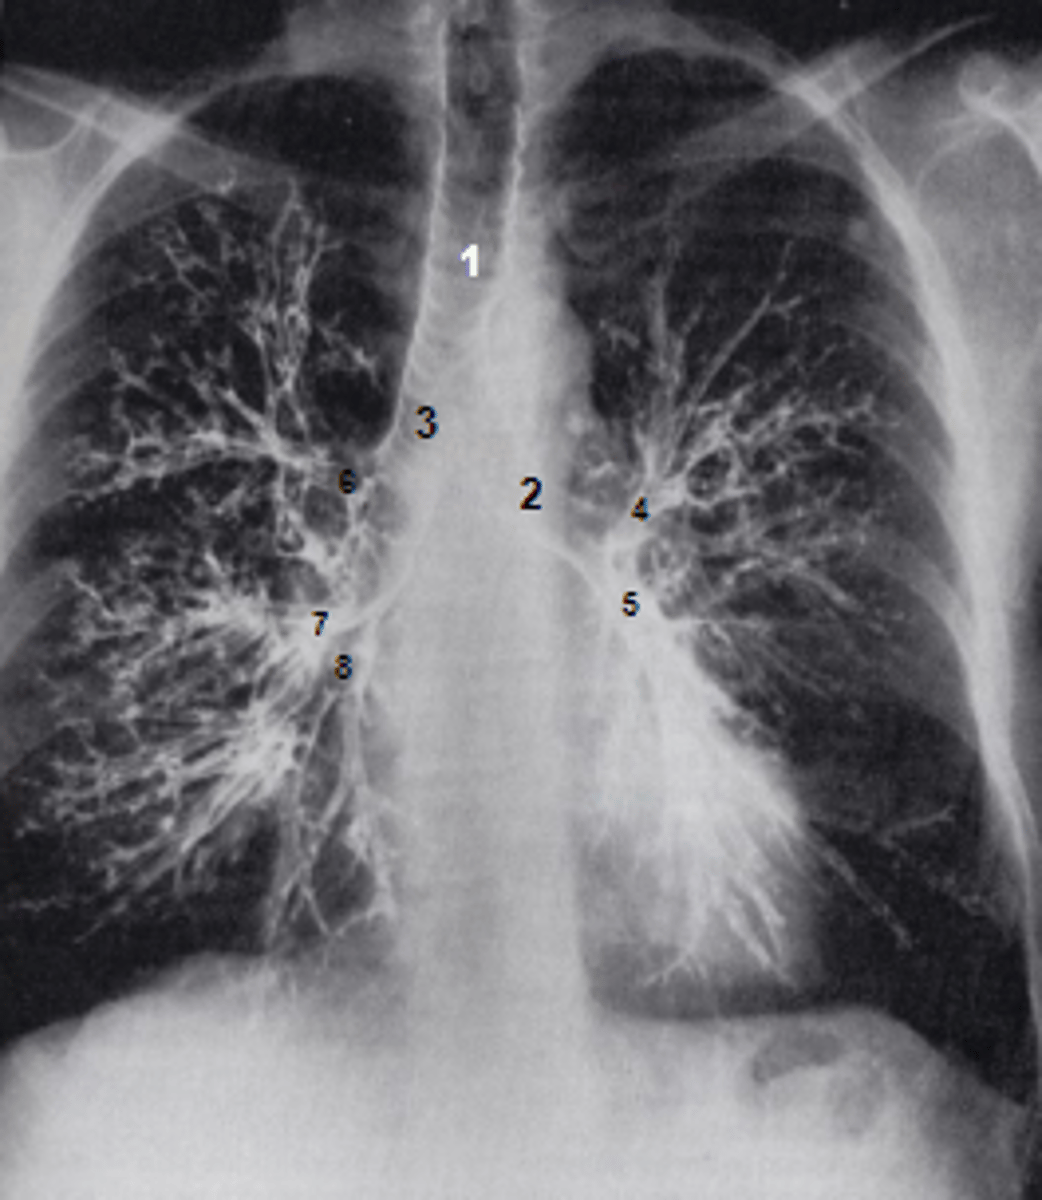

1

at what number is the trachea

2

at what number is the left main bronchus

3

at what number is the right main bronchus

4

at what number is the left superior lobar bronchus

5

at what number is the left inferior lobar bronchus

6

at what number is the right superior lobar bronchus

7

at what number is the right middle lobar bronchus

8

at what number is the right inferior lobar bronchus